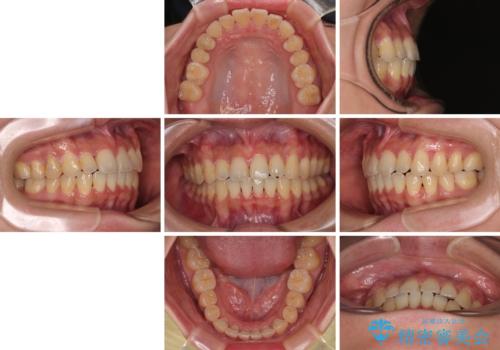

- メタルブラケット

- 1年4ヶ月

- 上下前歯のデコボコやクロスバイトを気にして来院された患者様です。

上顎歯列が下顎の歯列に対して狭小であり、一部下顎の奥歯が上顎よりも外側に位置している状態でした。

上顎の急速拡大装置を使用して上顎骨を側方に拡大することで上顎歯列を拡大し、下顎歯列も拡大できるようにすることで、歯列を整えることとしました。